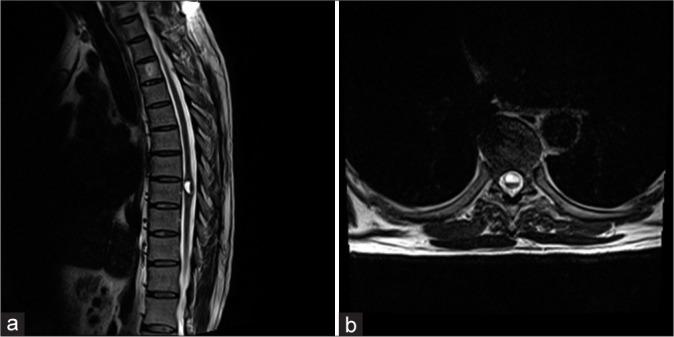

A 52-year-old male patient presented with rapidly progressive myelopathy and loss of ambulatory capabilities, with which magnetic resonance imaging revealed a hemorrhagic CM within the thoracic spinal cord. The CM was successfully resected through a minimally invasive tubular approach utilizing a dorsal root entry zone myelotomy. Postoperative imaging confirmed gross resection. His motor examination rapidly recovered, and he remains ambulatory with the use of a cane at a 2-year follow-up.

一名52岁男性患者出现快速进展的脊髓病和行走能力丧失,磁共振成像显示胸段脊髓内有一个出血性CM。通过利用背根入髓区切开术的微创管状入路成功切除了CM。术后影像学检查证实为全切。他的运动检查迅速恢复,在2年随访时,他使用拐杖仍能行走。